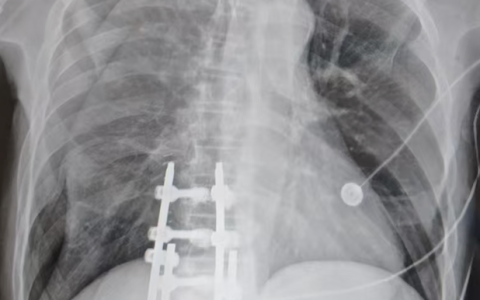

A 37 -year-old woman i s admitted to the ICU for severe pancreatitis(胰腺炎) complicated by acute respiratory distress syndrome (ARDS ) requiring mechanical ventilation. She continues to have difficulty ventilating and agitation(焦虑) on increasing doses of fentanyl(芬太尼) and midazolam(咪达唑仑) (Versed) IV infusions. What is the most appropriate next step ?

部分患者无论是否服用有效剂量的抗焦虑药物,均可保持谵妄、激越,难以维持通气。如果对患者进行气管插管、机械通气和充分镇静,使用神经肌肉阻滞使患者瘫痪是一个很好的选择。在通气困难且经常激越的 ARDS 患者中,神经肌肉阻滞可能是帮助改善通气和气体交换的合理替代方案。